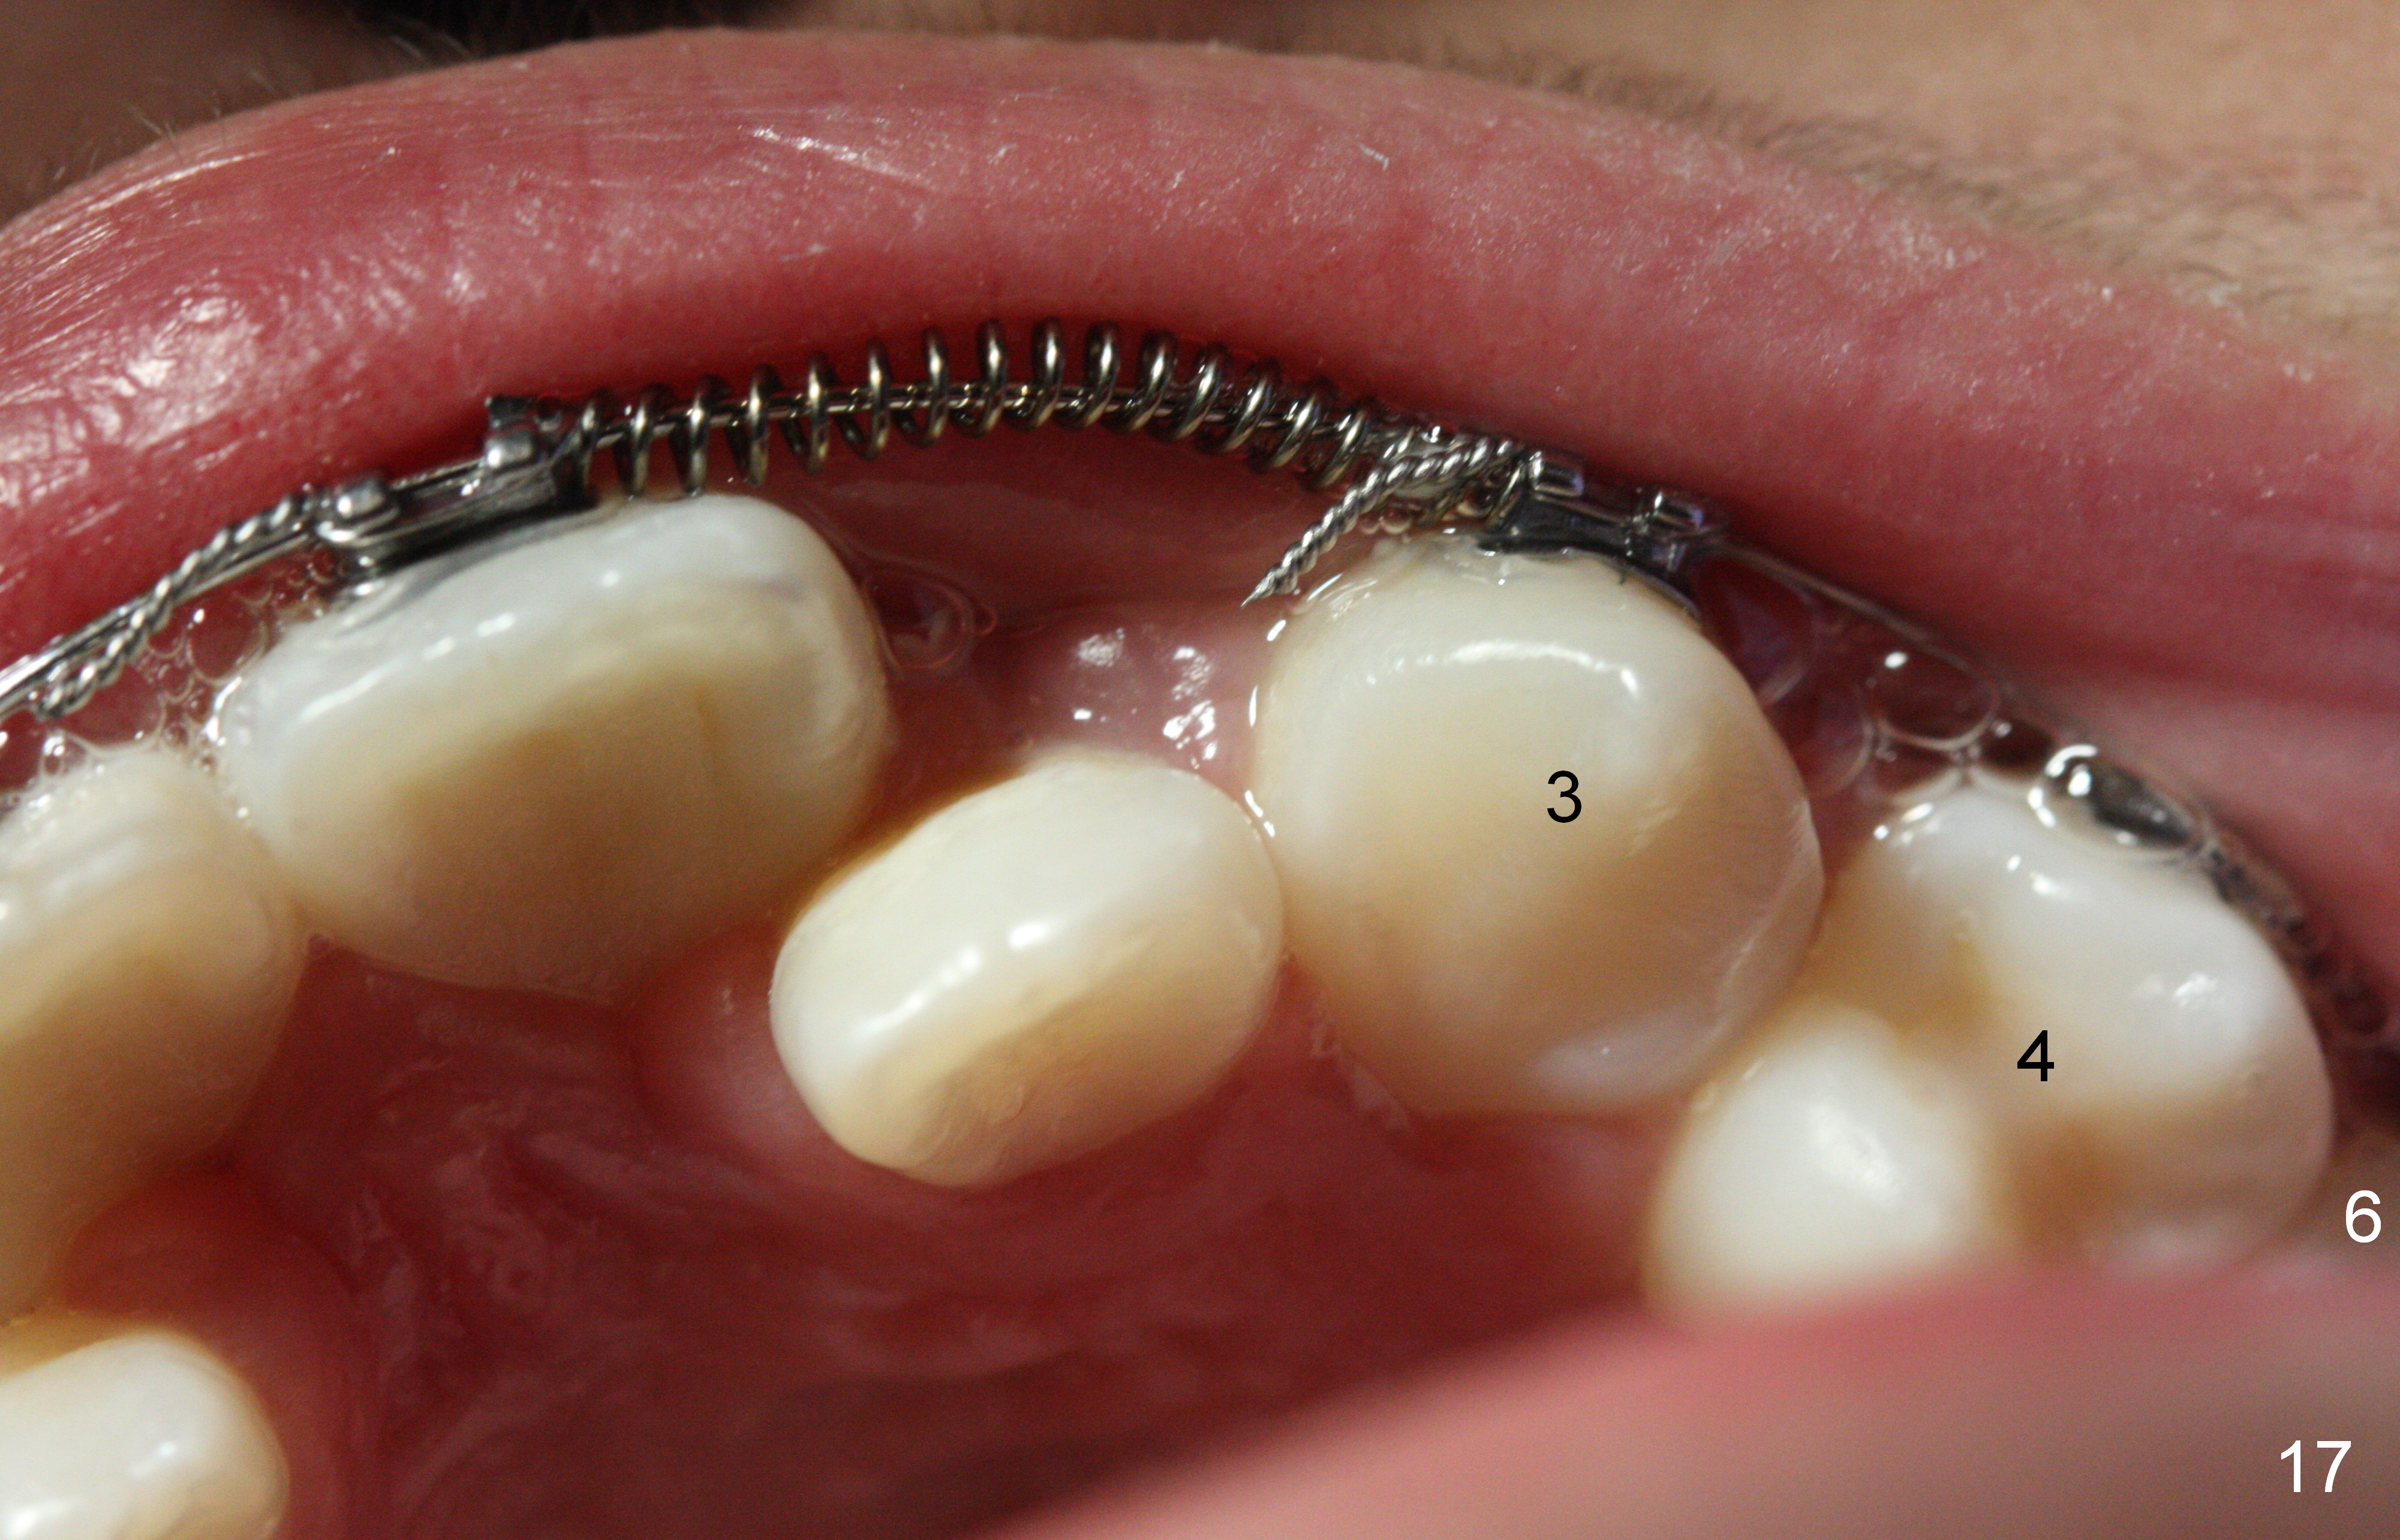

Another 1 month, the right canines (Fig.14: 3, as compared to the left side (Fig.15)) occlude each other, while LR2 has full engagement into .016 niti wire (compare to Fig.12,13). Open coil springs are placed with upper .018' ss arch wire. It must be easier to gain space for UR 2 (Fig.16) than UL2 (Fig.17), because of the presence of space on the right side (4 in Fig.16). There appears no space between UL 4 and 6.

Three visits after open coil spring and 1 visit after sling shot, U2 cross bite is corrected (Fig.18,19). Due to UR2 rotation (Fig.19), bracket cannot be placed (Fig.20, 16 niti). Power chain x 3 is placed between UR2 and 3 to gain space for bracketing, which turns out not working. UL2 bracket is placed upside down for torque.